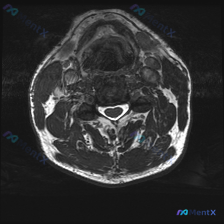

刚整理了一份很有启发的颈椎MRI读片病例,核心问题是“这张图里能观察到椎间盘病变吗?”,把完整分析思路分享给大家。 影像基本信息 这是一张颈椎MRI轴位T2加权图像,我们先把观察到的结构特征理清楚: 1. 椎体与椎管:脑脊液呈高信号,脊髓居中,形态规整,内部没有明显异常信号(无水肿灶);椎体后缘有轻...

整理了这张颈椎MRI读片病例和完整分析思路,分享给大家一起讨论 病例与影像基础信息 本次读片对象为颈椎MRI-T2序列轴位单张影像,核心问题是观察图像是否存在椎间盘病变: 1. 影像质量良好,对比度清晰,脊髓、脑脊液、软组织结构显示清楚,无明显运动伪影,扫描层面为颈椎中下段水平 2. 核心影像表现:...

刚看到一个有意思的读片病例,用户提供了一张颈椎MRI-T2序列轴位图像,明确提问是围绕「椎间盘病变」的观察,整理一下完整分析思路分享给大家。 一、影像基本信息 这是颈椎中下段的MRI-T2加权轴位图像,我们先按层次梳理客观观察结果: 1. 椎管与脊髓:脊髓位于椎管中央,形态规则,内部信号没有异常高/...